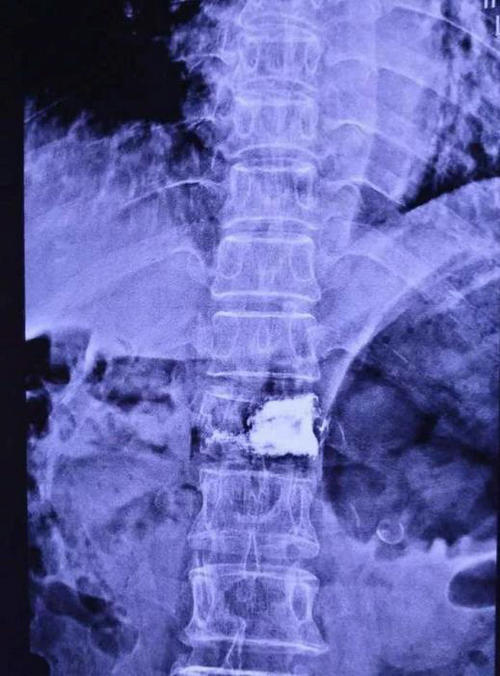

病人病情刻不容缓,应早日治疗,早日为高阿姨解除疼痛,早日出院。当日18点在局麻下,张主任为高阿姨成功实施微创手术,手术仅用时20分钟。术后高阿姨突然发现原来疼痛的部位顿时一点也不痛了。经过综合评估,全科讨论,认为高阿姨完全可以出院,于19点为高阿姨办理了出院手续。

▲ 患者术后正侧位影像